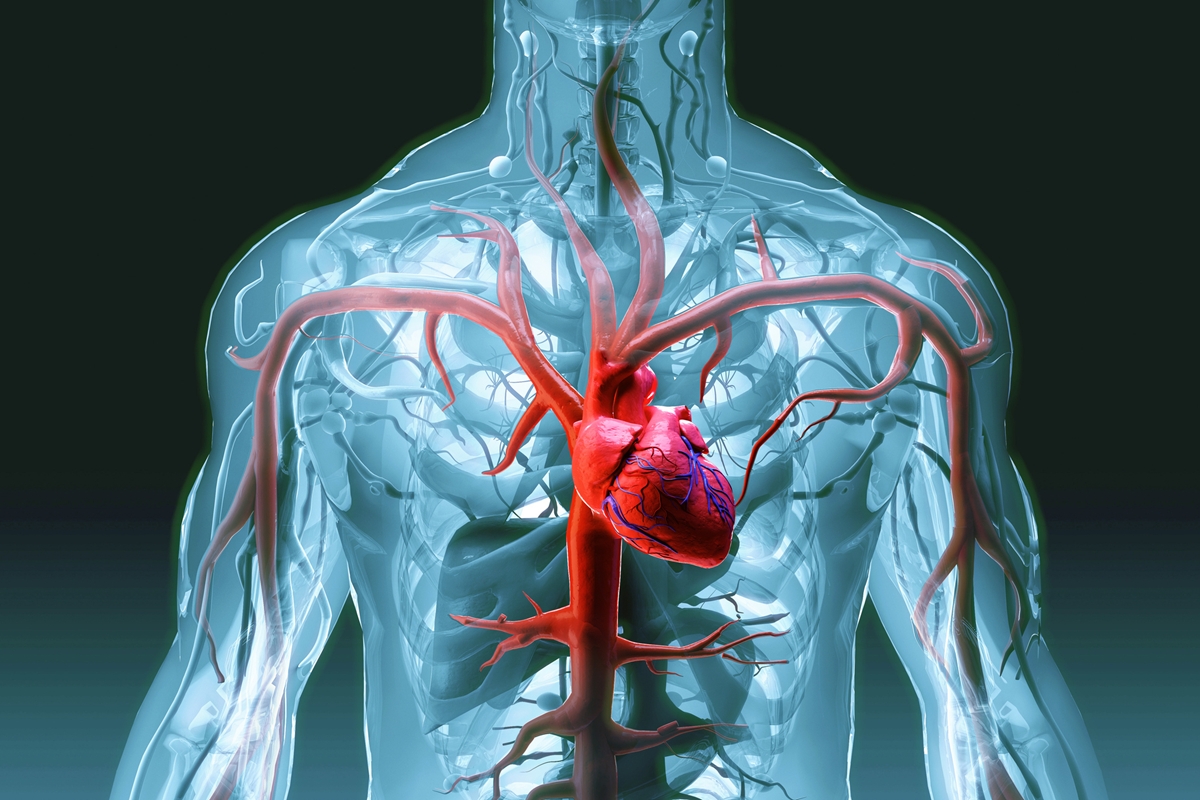

A pesquisa, publicada em 11 de fevereiro no Journal of the American College of Cardiology, acompanhou 200 mil pessoas ao longo de várias décadas. O objetivo foi entender como diferentes padrões alimentares influenciam o risco de doença cardíaca coronariana — condição causada pelo acúmulo de gordura nas artérias do coração.

O resultado da análise indicou que pessoas que seguiam versões saudáveis dessas dietas tiveram cerca de 15% menos risco de desenvolver doença cardíaca.

Esses dois fatores estão diretamente associados à redução do risco de infarto e outras doenças cardiovasculares. Segundo Zhiyuan Wu, mais importante do que escolher entre “baixo carboidrato” ou “baixa gordura” é priorizar alimentos naturais, ricos em fibras e nutrientes, e reduzir produtos ultraprocessados.